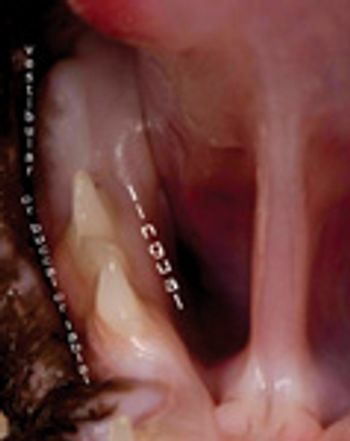

The lower jaw of the cat on your exam table is displaced to the left (Photo 1). Is the mandible or maxilla fractured? Or is the mandible luxated? If so, right or left? What is the best way to diagnose and treat this problem? Can you as a general practitioner handle it, or must the case be referred to a boarded orthopedic or dental specialist?